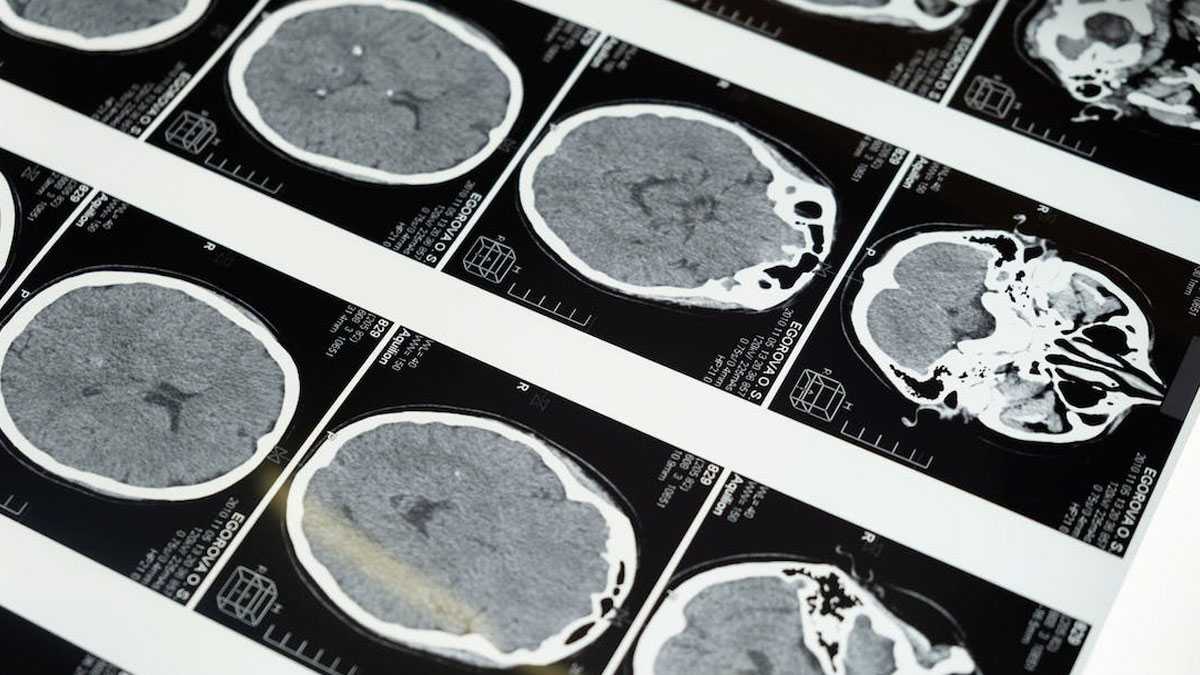

Para el estudio, la Dra. Ho y su equipo crearon modelos 3D en miniatura similares al cerebro, llamados organoides. Los grupos de células en 3D del tamaño de un guisante comenzaron como células sanguíneas de pacientes diagnosticados con trastorno por consumo de opioides. Las células sanguíneas se colocaron en una placa de cultivo y se "reprogramaron" hasta alcanzar un estado similar al de las células madre, denominado células madre pluripotentes inducidas. Estas denominadas células maestras pueden ser inducidas a convertirse en cualquier célula del cuerpo, incluidas las neuronas cerebrales.

"Las células crecen y se ensamblan por sí solas para replicar partes del cerebro, en este caso, la corteza prefrontal", dice la Dra. Ho. "Elegimos la corteza prefrontal porque en los estudios preclínicos y clínicos anteriores se ha identificado una implicación clave de esta región cerebral en la adicción".

A continuación, el equipo estudió los efectos de dos fármacos en los organoides (oxicodona y buprenorfina) y realizó un análisis de las vías de cada uno de ellos. La Dra. Ho y su equipo descubrieron vías biológicas relacionadas con la adicción a los opioides a nivel unicelular. Los resultados indican una relación entre la adicción a los opioides y la inflamación, que se produce cuando el sistema inmunitario del cerebro está hiperactivo.